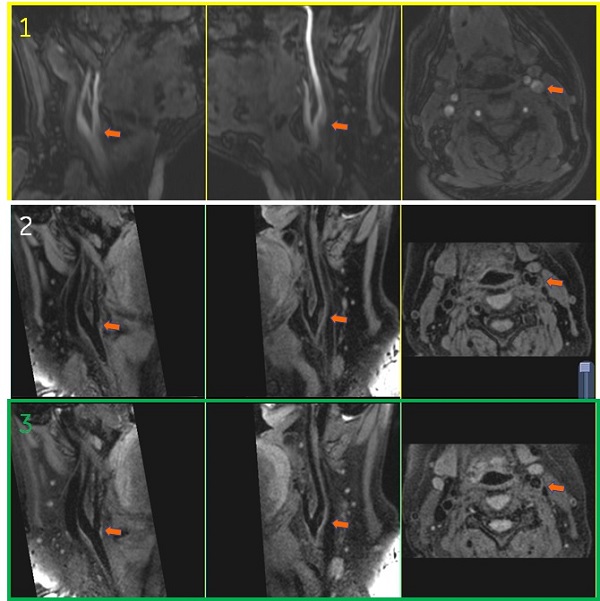

Figure 2. Images of in locally restricted B0 inhomogeneous regions

Table 3. Image legend

NumberDescription

1MSDE Off and Fast Recovery On.

2MSDE On and Fast Recovery Off. Note the signal loss.

Figure 3. Images with Fast Recovery on and off

Table 4. Image legend

1Cube with MSDE and Fast Recovery OnCV22 = 3, CV29 = 1

2Cube with MSDE and Fast Recovery Off

CV22= 3, CV29= 1

By turning off Fast Recovery, contrast between vessel wall and vessel lumen became high. On the other hand, contrast between white matter, gray matter and CSF became low.